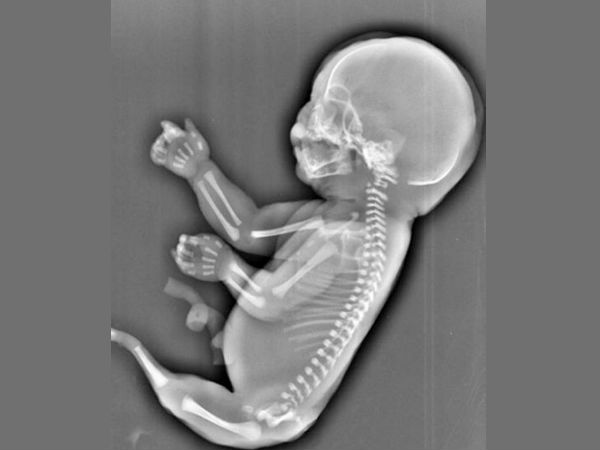

“மாதா மாதம் வரவேண்டிய மாதவிடாய் ஆகவேண்டிய நாளாகியும் இன்னும் வரவில்லையே! ஒருவேளை நான் கருத்தரித்துவிட்டேனா?” என்று நாற்பது, நாற்பத்தைந்து நாட்களுக்குப் பிறகுதானே கர்ப்பமாக இருப்பதைப் பற்றியே நீங்கள் சிந்திக்க ஆரம்பிப்பீர்கள். ஆனால் அதற்கு முன்பாகவே அதாவது கருத்தரித்த இருபதாவது நாளின் அருகாமையிலேயே உங்களது சுட்டிக் குழந்தையின் இதயமும், மூளையும் உருவாகிவிடுகிறது. அதற்கு அடுத்த வாரத்திலேயே இதயம் துடிக்கவும் ஆரம்பித்துவிடுகிறது. இப்படி உங்களது குழந்தையின் மூளையும், இதயமும் சீக்கிரமாக உருவாகி வேலை செய்யத் துவங்கினால் தானே நீங்கள் மசக்கையாக இருப்பதே உங்களுக்குத் தெரியவரும்! என்ன, இது புதிராக இருக்கிறதல்லவா?

ஆம், நீங்கள் கருத்தரித்த நாளிலிருந்து மூன்றாவது வாரத்திலேயே குழந்தையின் இதயம் உருவாகிவிடுகிறது. இன்று கல்லூரி இளைஞர்கள் அம்பு விட்டபடி வரையும் இதயத்தைப் போலல்லாமல் அது ஓரளவிற்கு இரசிக்கக்கூடியதாக, குழந்தை வளருவதற்குத் தேவையான ரத்தத்தை உடல் முழுவதும் செலுத்தும் அளவிற்கு முதிர்ச்சி பெற்றதாக உருவாகிவிடுகிறது. ஆனால் இதயம் உருவாகினால் மட்டும் போதுமா? அவை துடிக்க வேண்டாமா? அப்படியே துடித்தாலும் தாறுமாறாகத் துடித்துவிட்டால், என்ன செய்வது?

இன்றைய காலத்து இளைஞர்கள் காதலித்துவிட்டு அதைக் காதலியிடம் சொல்லப்போகும் போது இதயம் தாறுமாறாகத் துடிக்குமே! அப்பப்பா!! இதயமே கழன்று வெளியில் வந்து விழுந்துவிடுவது போலிருக்கும். காதலிப்பவர்களுக்காகவே உதவி செய்வதற்கென்று சில அருமையான நண்பர்கள் இருப்பார்களல்லவா. அது போலத்தான் குழந்தையின் இதயத்தின் துடிப்பைக் கட்டுப்படுத்தி, ஒரே சீரான சங்கீதமாகத் துடிக்க வைக்க உதவுவதற்காகவும் கூடவே மூளையாகிய நண்பனும் மூன்றாவது வாரத்திலேயே வளர்ந்துவிடுகிறது. அத்தகைய மூளையின் உதவியால்தான் உங்கள் சுட்டிக் குழந்தையின் இருதயமும் நிமிடத்திற்கு சீராக 140 முதல் 160 வரை துடிக்கிறதென்றால் பார்த்துக் கொள்ளுங்கள்.

“அம்மாடியோவ்! இதயம் இவ்வளவு வேகமாவா துடிக்குது?” என்று ஆச்சரியப்படுவதில் ஒன்றுமே இல்லை. பெரியவர்களாக இருக்கிற உங்களுக்கு வேண்டுமானால் சாதாரணமாக நிமிடத்திற்கு 60 முதல் 100க்குள் சராசரியாக இதயம் துடிக்கலாம். ஆனால் கருவாக இருந்து வேகமாக வளர்ந்து கொண்டிருக்கும் உங்கள் குழந்தைக்குத்தான் அதிகமான போஷாக்கு தேவைப்படுமே! அத்தகைய போஷாக்கே தொப்புள்கொடி வழியே குழந்தைக்குப் பாய்ந்தோடுகிற அம்மாவின் இரத்தம் தானே! அப்படிப்பட்ட இரத்தத்தின் தேவையைப் பூர்த்தி செய்வதற்காகத்தான் குழந்தையின் இதயமானது இப்படி வேகமாகத் துடிக்கிறது.

கருவிலே இதயமும், மூளையும் உருவாகி அவை வேலை செய்ய ஆரம்பிக்கும் வேளையில் தான் கர்ப்பவதியான உங்களுக்கு மசக்கையே ஆரம்பிக்கும். அதாவது சிசுவின் உடம்புக்குள் ரத்தம் பாய்ந்து செல்வதால் அப்போது தான் உங்களது ரத்தமும் சிசுவினுடைய ரத்தமும் தொப்புள்கொடி வழியாக நஞ்சுப் பகுதியில் சந்திக்கிறது. கருத்தரித்த மூன்றாவது அல்லது நான்காவது வாரம் வரை எதுவுமே நடக்காதது போலிருக்கும் உங்களது உடம்போ அப்போதுதான் சுருக்கென்று முள் குத்தியதைப்போல “இரத்தத்துல என்னமோ நடக்குது. ஆனா என்னான்னு தெரியலையே?” என்று குழம்பிக் கொண்டிருக்கும். அத்தகைய குழப்பம்தான் மசக்கையே!